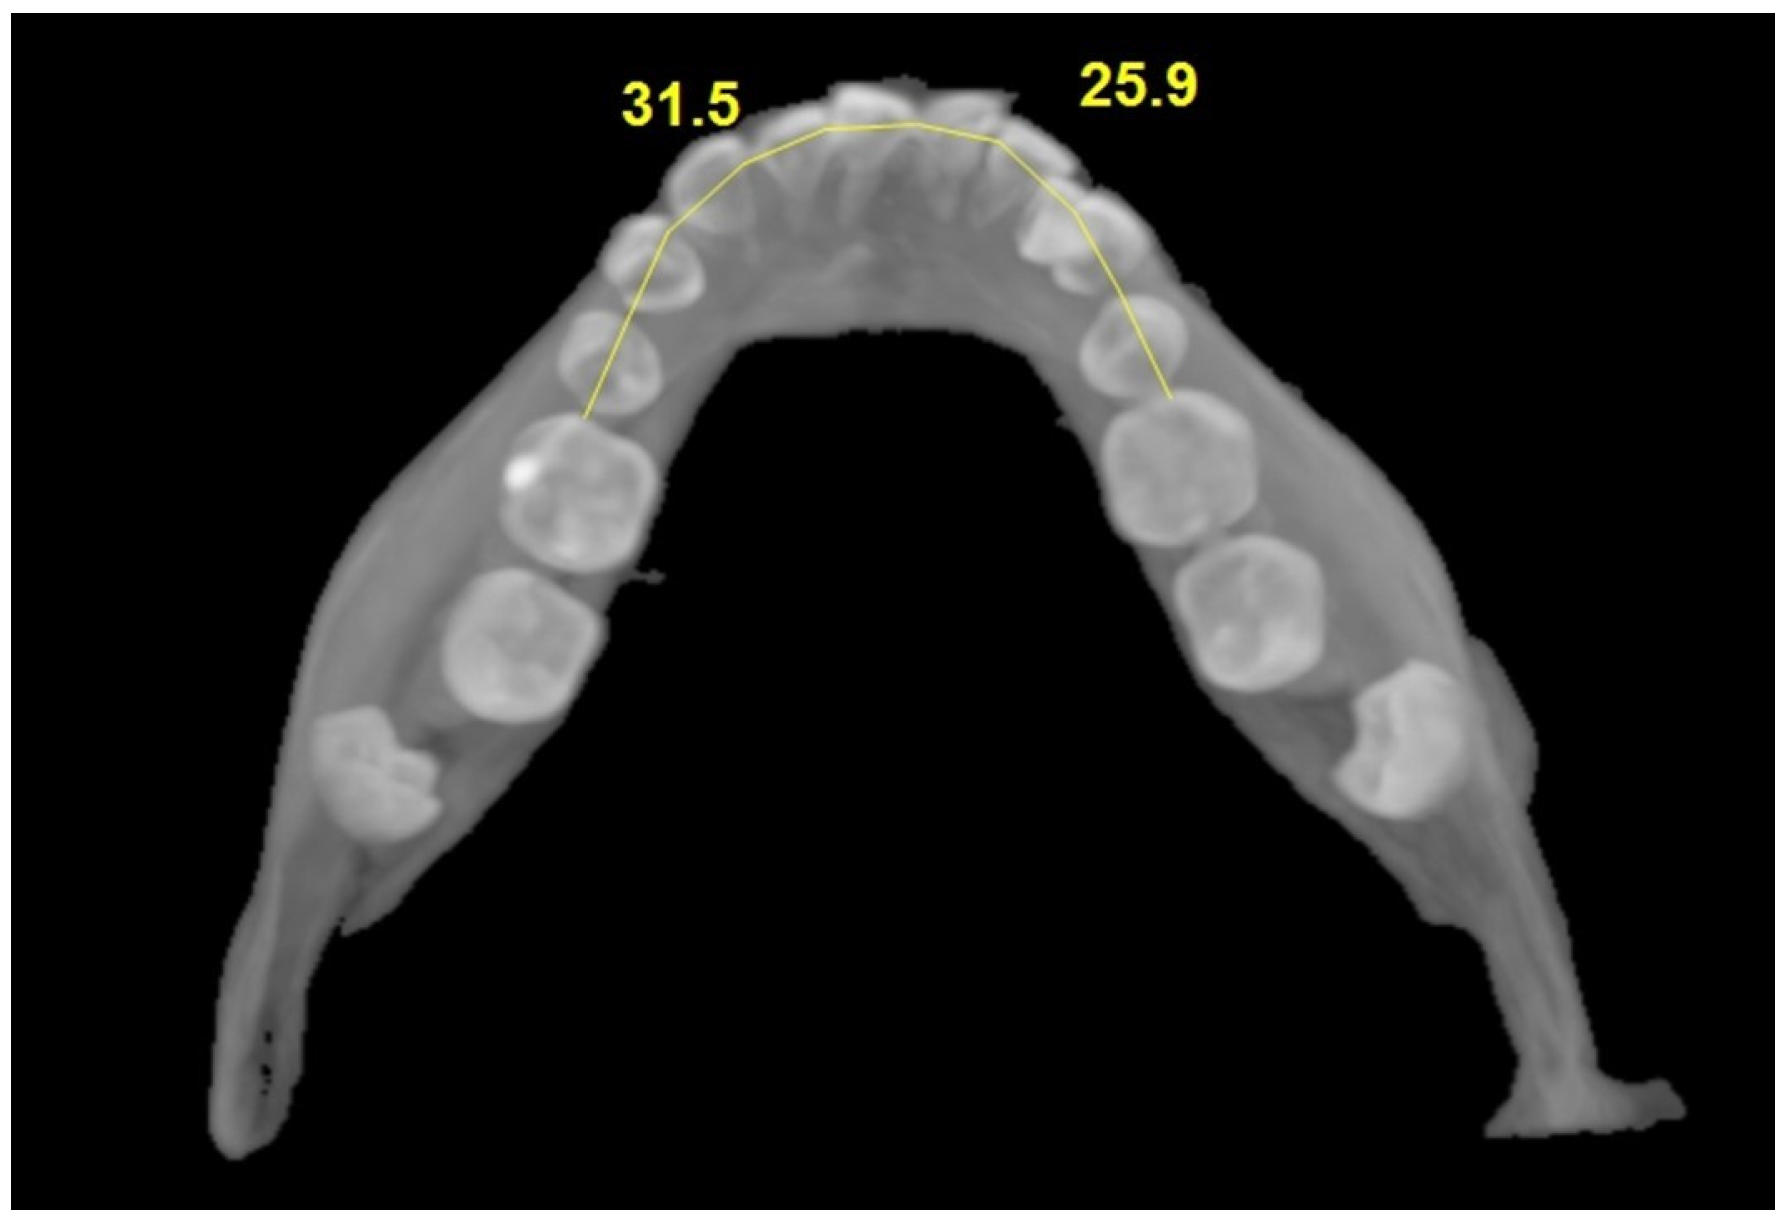

| Arch length | 29.92 ± 2.38 | 32.21 ± 2.18 | t = 5.194 | <0.001 |

| 30.05 (2.80) | 32.40 (3.00) | |||